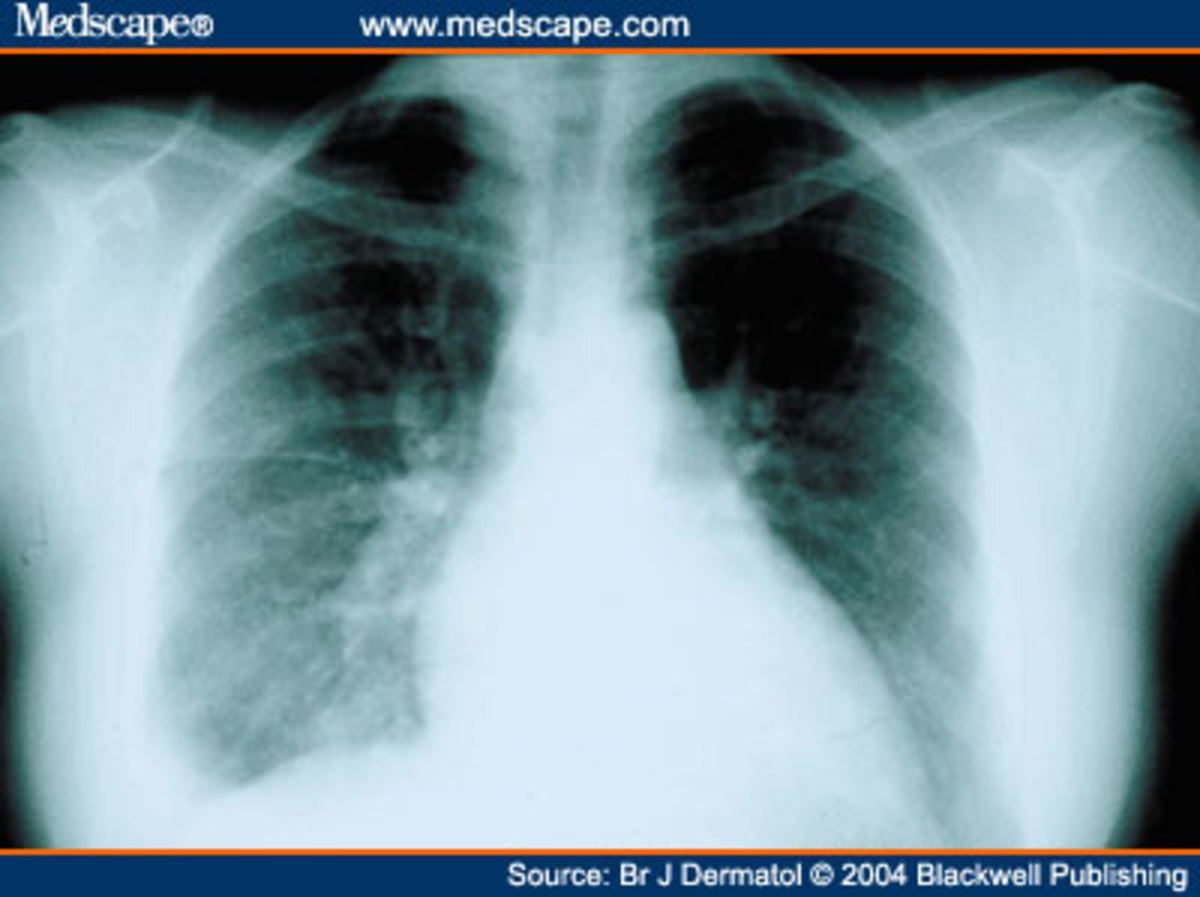

Pleural Plaques On Chest X Ray Can Pleural Plaques Cause Pain  They are generally seen as a marker of past. many persons, often those who have only had brief exposure, develop pleural plaques. pleural plaques are areas of tissue that become thickened in the lining of the lungs.  pleural plaques are distinct from dpt, which consists of extensive fibrosis of the visceral pleura, often.  pleural plaques can. Can Pleural Plaques Cause Pain.

Pleurisy In Chest XRay Various Radiographs To Show And Depict This Can Pleural Plaques Cause Pain  many persons, often those who have only had brief exposure, develop pleural plaques.  also called pleuritis, pleurisy causes sharp chest pain (pleuritic pain) that worsens during breathing. They are generally seen as a marker of past.  pleural plaques are distinct from dpt, which consists of extensive fibrosis of the visceral pleura, often.  an injury, inflammation ,. Can Pleural Plaques Cause Pain.

Pleurisy, Xray Stock Image M240/0731 Science Photo Library Can Pleural Plaques Cause Pain   pleural plaques can be a sign of exposure to asbestos, which can increase someone’s risk of developing fatal. One pleural layer of tissue wraps around. pleural plaques are areas of tissue that become thickened in the lining of the lungs.  also called pleuritis, pleurisy causes sharp chest pain (pleuritic pain) that worsens during breathing.  pleuritic chest. Can Pleural Plaques Cause Pain.